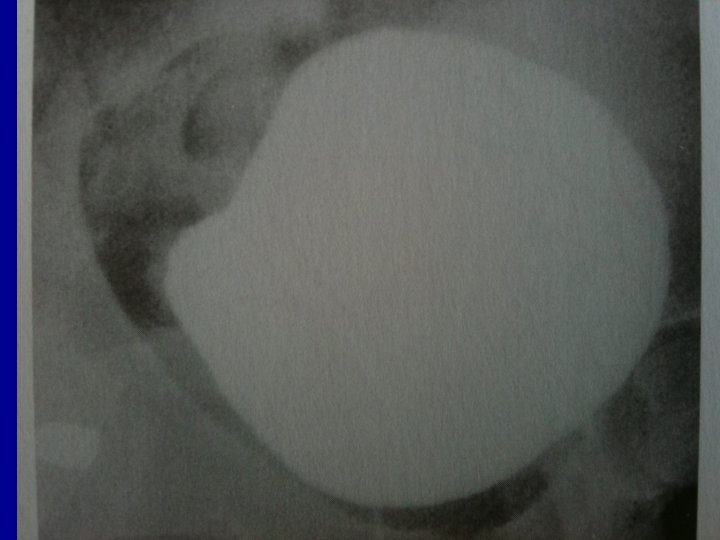

Bladder Repair • 10 % of pelvic Fx are associated with bladder rupture • 94% have gross hematuria • Dx established by CT cystogram • extraperitoneal 58 % • Intraperitoneal 33 % • combined 10 %

Bladder Repair • Carefully evaluated bladder • If injury present, open dome of the bladder in midline • Inspect bladder from the inside • Locate ureteral orifices and urethra •

• Repair extraperitoneal injuries from the inside • Single layer of interrupted 2 -0 or 3 -0 absorbable • Intraperitoneal rupture is closed with 2 layers of running absorbable suture